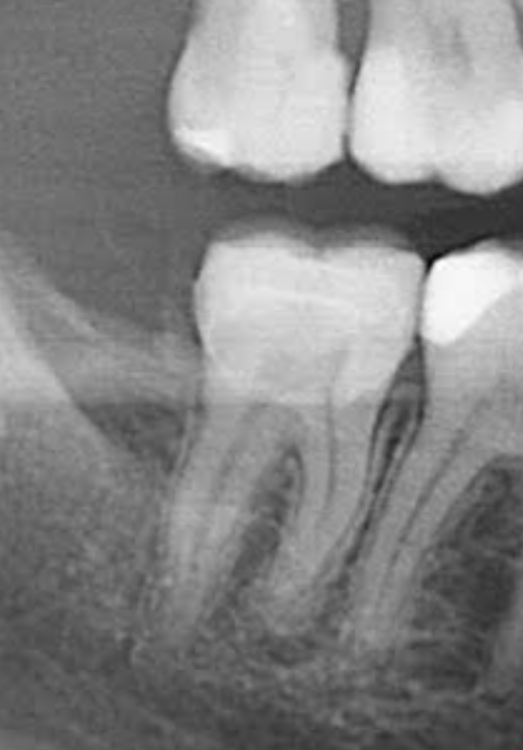

Рекомендовали вместо пломбы установить вкладку на 7-й нижний правый зуб. Нерв не удаляли. С момента установки прошло 9 дней и все время болит при надавливании, жевании. На холод/горячее не реагирует. Врач немного подтачивал вкладку, но особо не повлияло. Что может быть? Надо удалять нерв?

Screenshot 2022-07-06 at 20.27.08.png